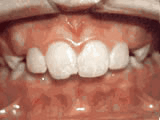

Phase One

Patient's parents were concerned about both aesthetics and the health of the erupting permanent teeth when they brought him to the orthodontist at age eight. The lower front teeth were crowded and touching the palate, and the upper front teeth were extremely displaced from their normal positions. After 12 months of Phase One treatment with an expander and partial braces, patient's appearance and dental function were vastly improved.